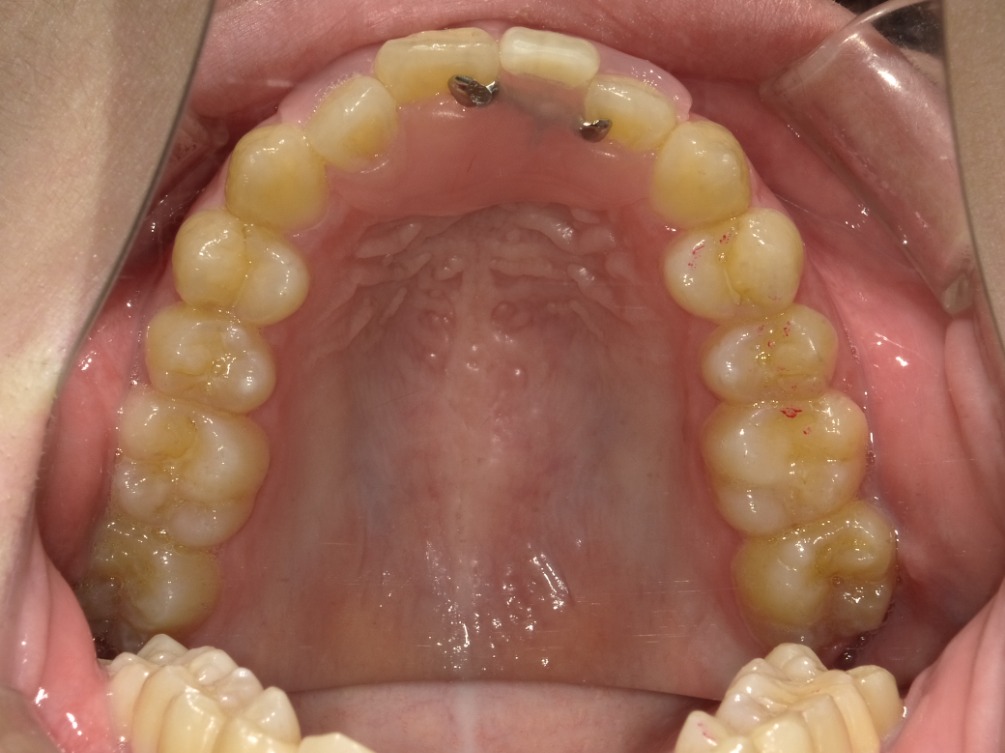

上顎

| 治療内容 | インビザライン 全顎〈抜歯あり〉 |

| 治療詳細 | 叢生や交叉咬合を整えるために、歯の表面にアタッチメント(白い突起)をつけ、IPR(歯と歯の間を削る)を行いました。 また、顎間ゴムと呼ばれる引っ掛けるゴムの補助装置も用いて治療を行いました。 抜歯を1本して治療を行いました。該当部分は義歯を使用しています。 |

| 患者情報 | 20代 女性 デンタルモニタリング使用 |

| 主訴 | 歯のがたつき 一部分だけかみ合わせが反対 |